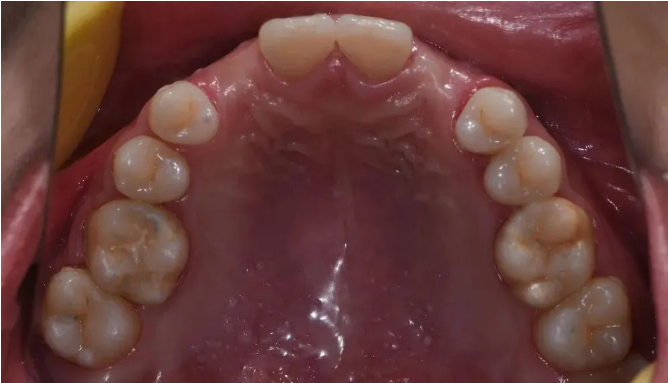

口内检查

12、13、22、23先天缺失

患者缺牙间隙偏宽,唇侧轮廓轻度塌陷,息止颌位切端暴露量正常